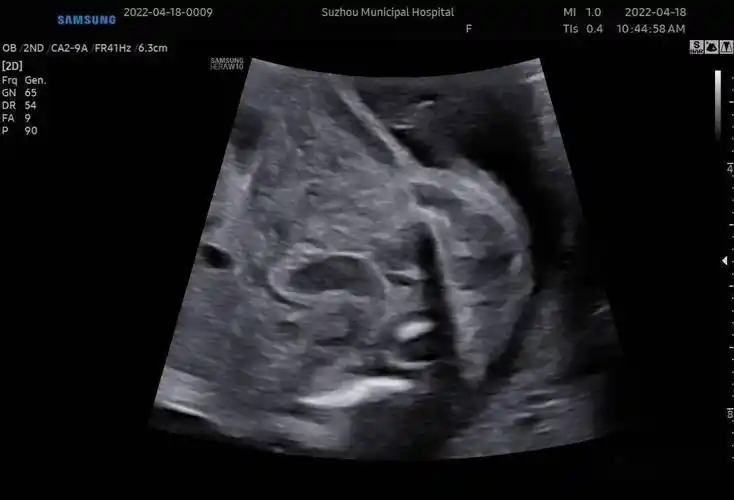

诊断胎儿尿道下裂前请先搞清男女!